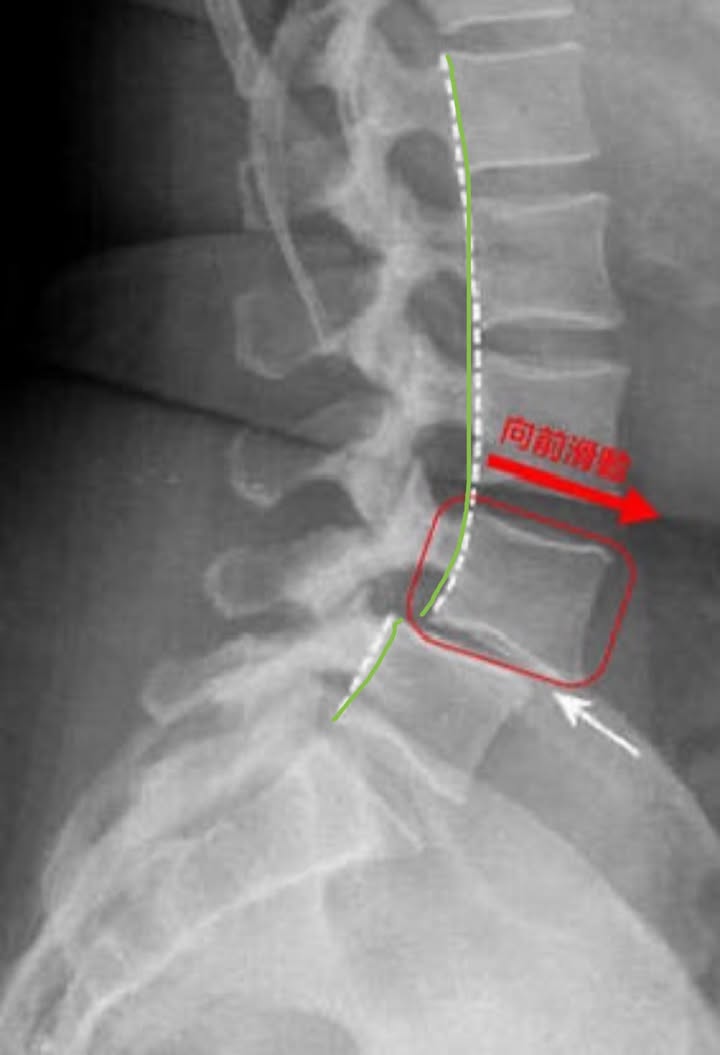

又讓一個脊椎滑脫的患者畢業了,看到患者真心回饋真的超開心的,所謂脊椎滑脫是指椎體往前或往後位移,最常發生於腰部,大部份患者係因長期久坐、搬重物時使力不當、重覆性過度彎腰及轉腰、以及習慣性駝背凸肚等不良姿勢,而使得軟組織和小面關節受損退化且鬆脫,導致腰椎滑脫,這一類病灶多為腰椎第四節與第五節。